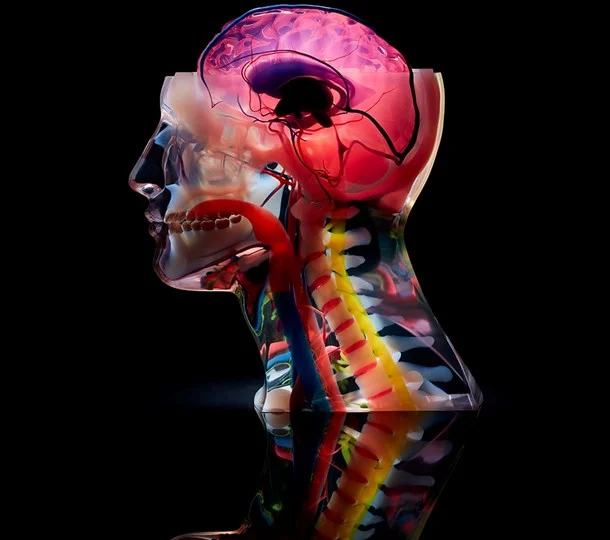

Custom anatomical models

High-quality anatomical models are expensive and offer a finite set of options for the best. The templates are routinely used by students and professionals for education, training, surgical planning, and visual aids for patients.

With affordable 3D printing services, medical professionals and educators can create customized anatomical models at a low cost for various purposes. For example, surgeons can perform complex procedures using patient-specific models that accurately simulate the situations they may face during surgery.